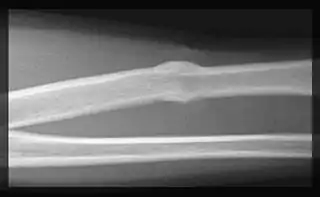

Callo óseo

Un callo óseo (latín: callus) es una formación temporal de fibroblastos y condroblastos en la zona de fractura de un hueso, mientras que el hueso intenta regenerar. Es la secuela reparadora de una fractura ósea.

Es el depósito óseo formado entre y alrededor de los extremos rotos de un hueso fracturado durante su osificación reparadora.[1]

Un callo óseo está constituido por tejido óseo esponjoso inmaduro que temporalmente inmoviliza los fragmentos de una fractura, y asegura la continuidad del hueso fracturado mientras se restablece la continuidad de los sistemas de Havers de los fragmentos.

El callo de fractura se subdivide en callo óseo interno, constituido por un tejido óseo esponjoso inmaduro formado por osificación intramembranosa, y callo óseo externo, constituido por un tejido óseo esponjoso inmaduro formado por osificación intramembranosa y endocondral. Una vez establecida la continuidad del tejido óseo, cesa la necesidad de un callo de fijación y ambos callos, interno y externo, se reabsorben.[2][3]

La forma habitual de valorar su formación y evolución es mediante radiografía del hueso fracturado.